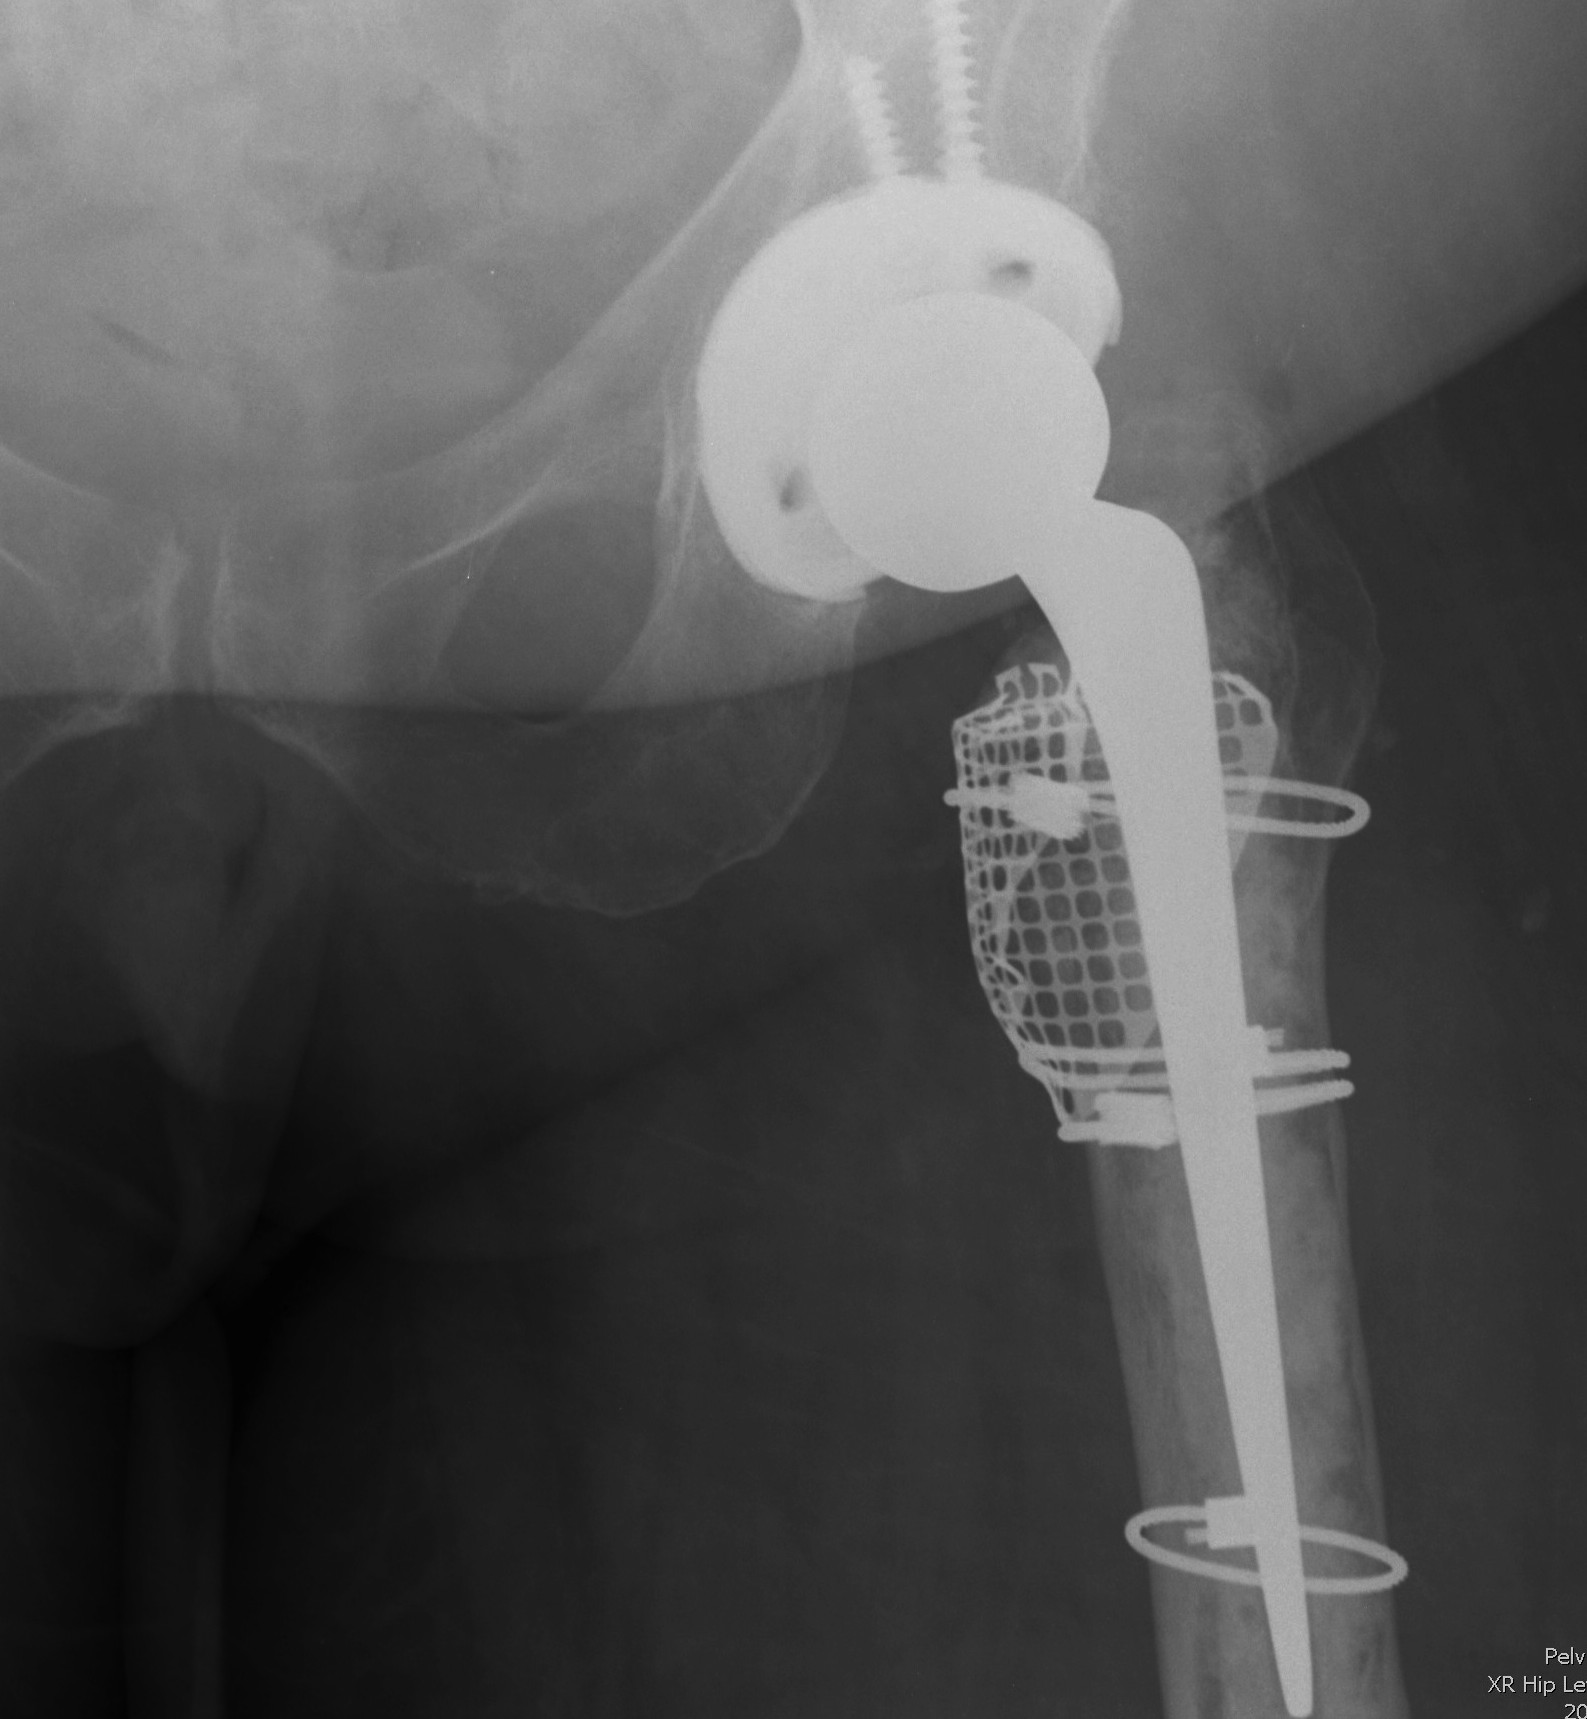

4. Impaction bone grafting

Requirements

1. Particulate cancellous autograft 7-10 mm

2. Contained defect

3. Ability to convert uncontained into contained (i.e. mesh)

Issues

- technically demanding

- takes time

- need axial and rotational stability

- avoid stem subsidence > 5 mm

Create contained defect

- reconstitute femoral tube

- create contained defect

- wire mesh & cerclage wire

- prophylactically cerclage wire shaft if diaphysis flimsy

- cemented polished collarless double tapered stem